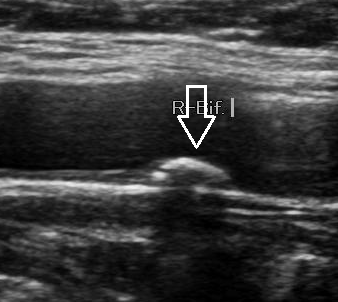

경동맥 초음파(Carotid Ultrasound)는 목 양쪽에 위치한 경동맥(carotid artery)의 혈류 상태를 확인하는 비침습적 영상 진단법입니다. 경동맥은 뇌로 혈액을 공급하는 주요 동맥으로, 이 부위에 죽상경화(동맥경화)가 발생하면 뇌졸중(중풍)이나 일과성 허혈 발작(TIA) 등 치명적인 뇌혈관 질환으로 이어질 수 있습니다.

이 검사는 초음파를 통해 경동맥 내벽의 두께, 혈류 속도, 혈전이나 협착(좁아진 부분) 여부 등을 정밀하게 경동맥 초음파 검사로 알 수 있는 병들을 관찰하여, 뇌졸중 위험성을 사전에 파악할 수 있는 중요한 예방 의료 행위입니다.

- 초음파 검사 시행

- 침대에 누워 목 양쪽에 초음파 탐촉자(probe)를 대고 관찰

- 통증 없음, 검사 시간 약 10~20분 소요